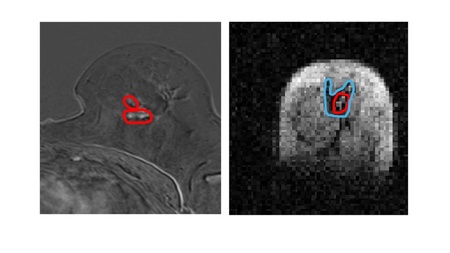

Scientists from the University, in collaboration with NHS Grampian, used a prototype version of the new Field Cycling Imager (FCI) scanner to examine the breast tissue of patients newly diagnosed with cancer. They found that the FCI scanner could distinguish tumour material from healthy tissue with more accuracy than current MRI methods.

While similar to MRI in that MRI uses strong magnetic fields and radio waves to produce detailed images of the inside of the body without touching it - the FCI scanner can vary the strength of the magnetic field during the patient’s scan.  This means the FCI acts like multiple scanners in one and can extract multiple different types of information about the tissue.